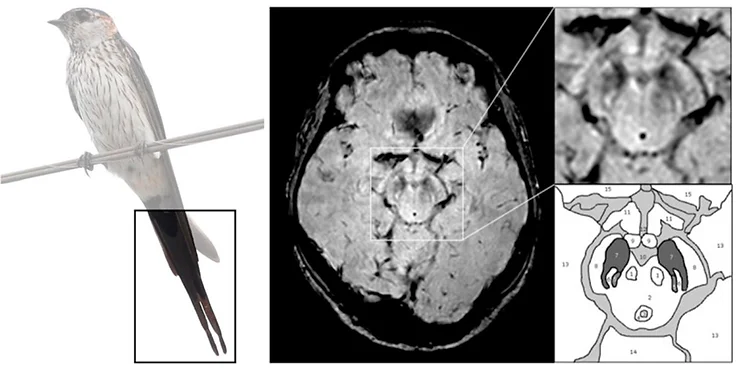

Neste artigo, foram investigadas a viabilidade da detecção e a avaliação de alterações na cauda da andorinha usando-se ressonância magnética (3T) em 114 pacientes. Foram comparados os achados de ressonância entre pacientes com doença de Parkinson e indivíduos saudáveis. Primeiramente, a cauda da andorinha foi passível de detecção. Abaixo, uma pequena comparação gráfica da cauda de uma andorinha com a imagem gerada por ressonância magnética na substância negra, usando a técnica de imagem ponderada na susceptibilidade (SWI) em pacientes saudáveis no estudo:

Aqui, o nigrossoma-1 está localizado no terço posterior da substância negra em formato linear, de 'vírgula' ou 'cunha' e é cercado por baixa intensidade de sinal em SWI anterior e lateralmente (pars compacta) e medialmente por baixo sinal no leminísco medial (fig. 1). O Nigrossoma-1 e suas estruturas circundantes possuem semelhança com a cauda de uma andorinha na imagem axial (HR-SWI).

Entretanto, quando comparadas estas imagens com as de indivíduos com a doença de Parkinson, a cauda da andorinha (nigrossoma-1) encontra-se ausente bilateralmente. Ou seja, a ressonância magnética foi capaz de detectar a perda tecidual ocorrida na região associada ao o desenvolvimento da patologia.